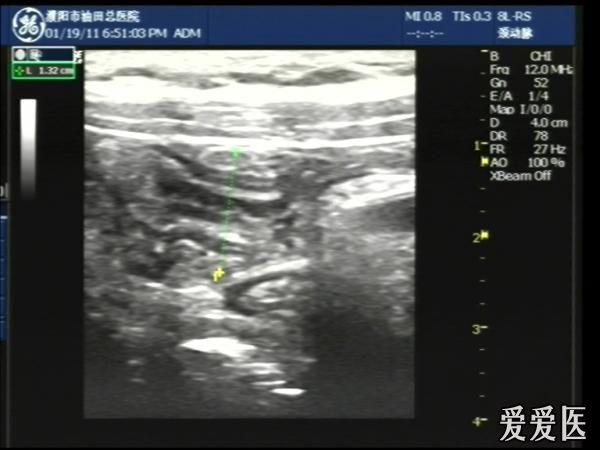

超声检查:于下腹部可见“双环征象”,双环重叠长约6mm,检查期间观察可见肠蠕动;CDFI:未见明显异常血流信号。

超声提示:下腹部双环征,考虑肠套叠可能,请结合临床